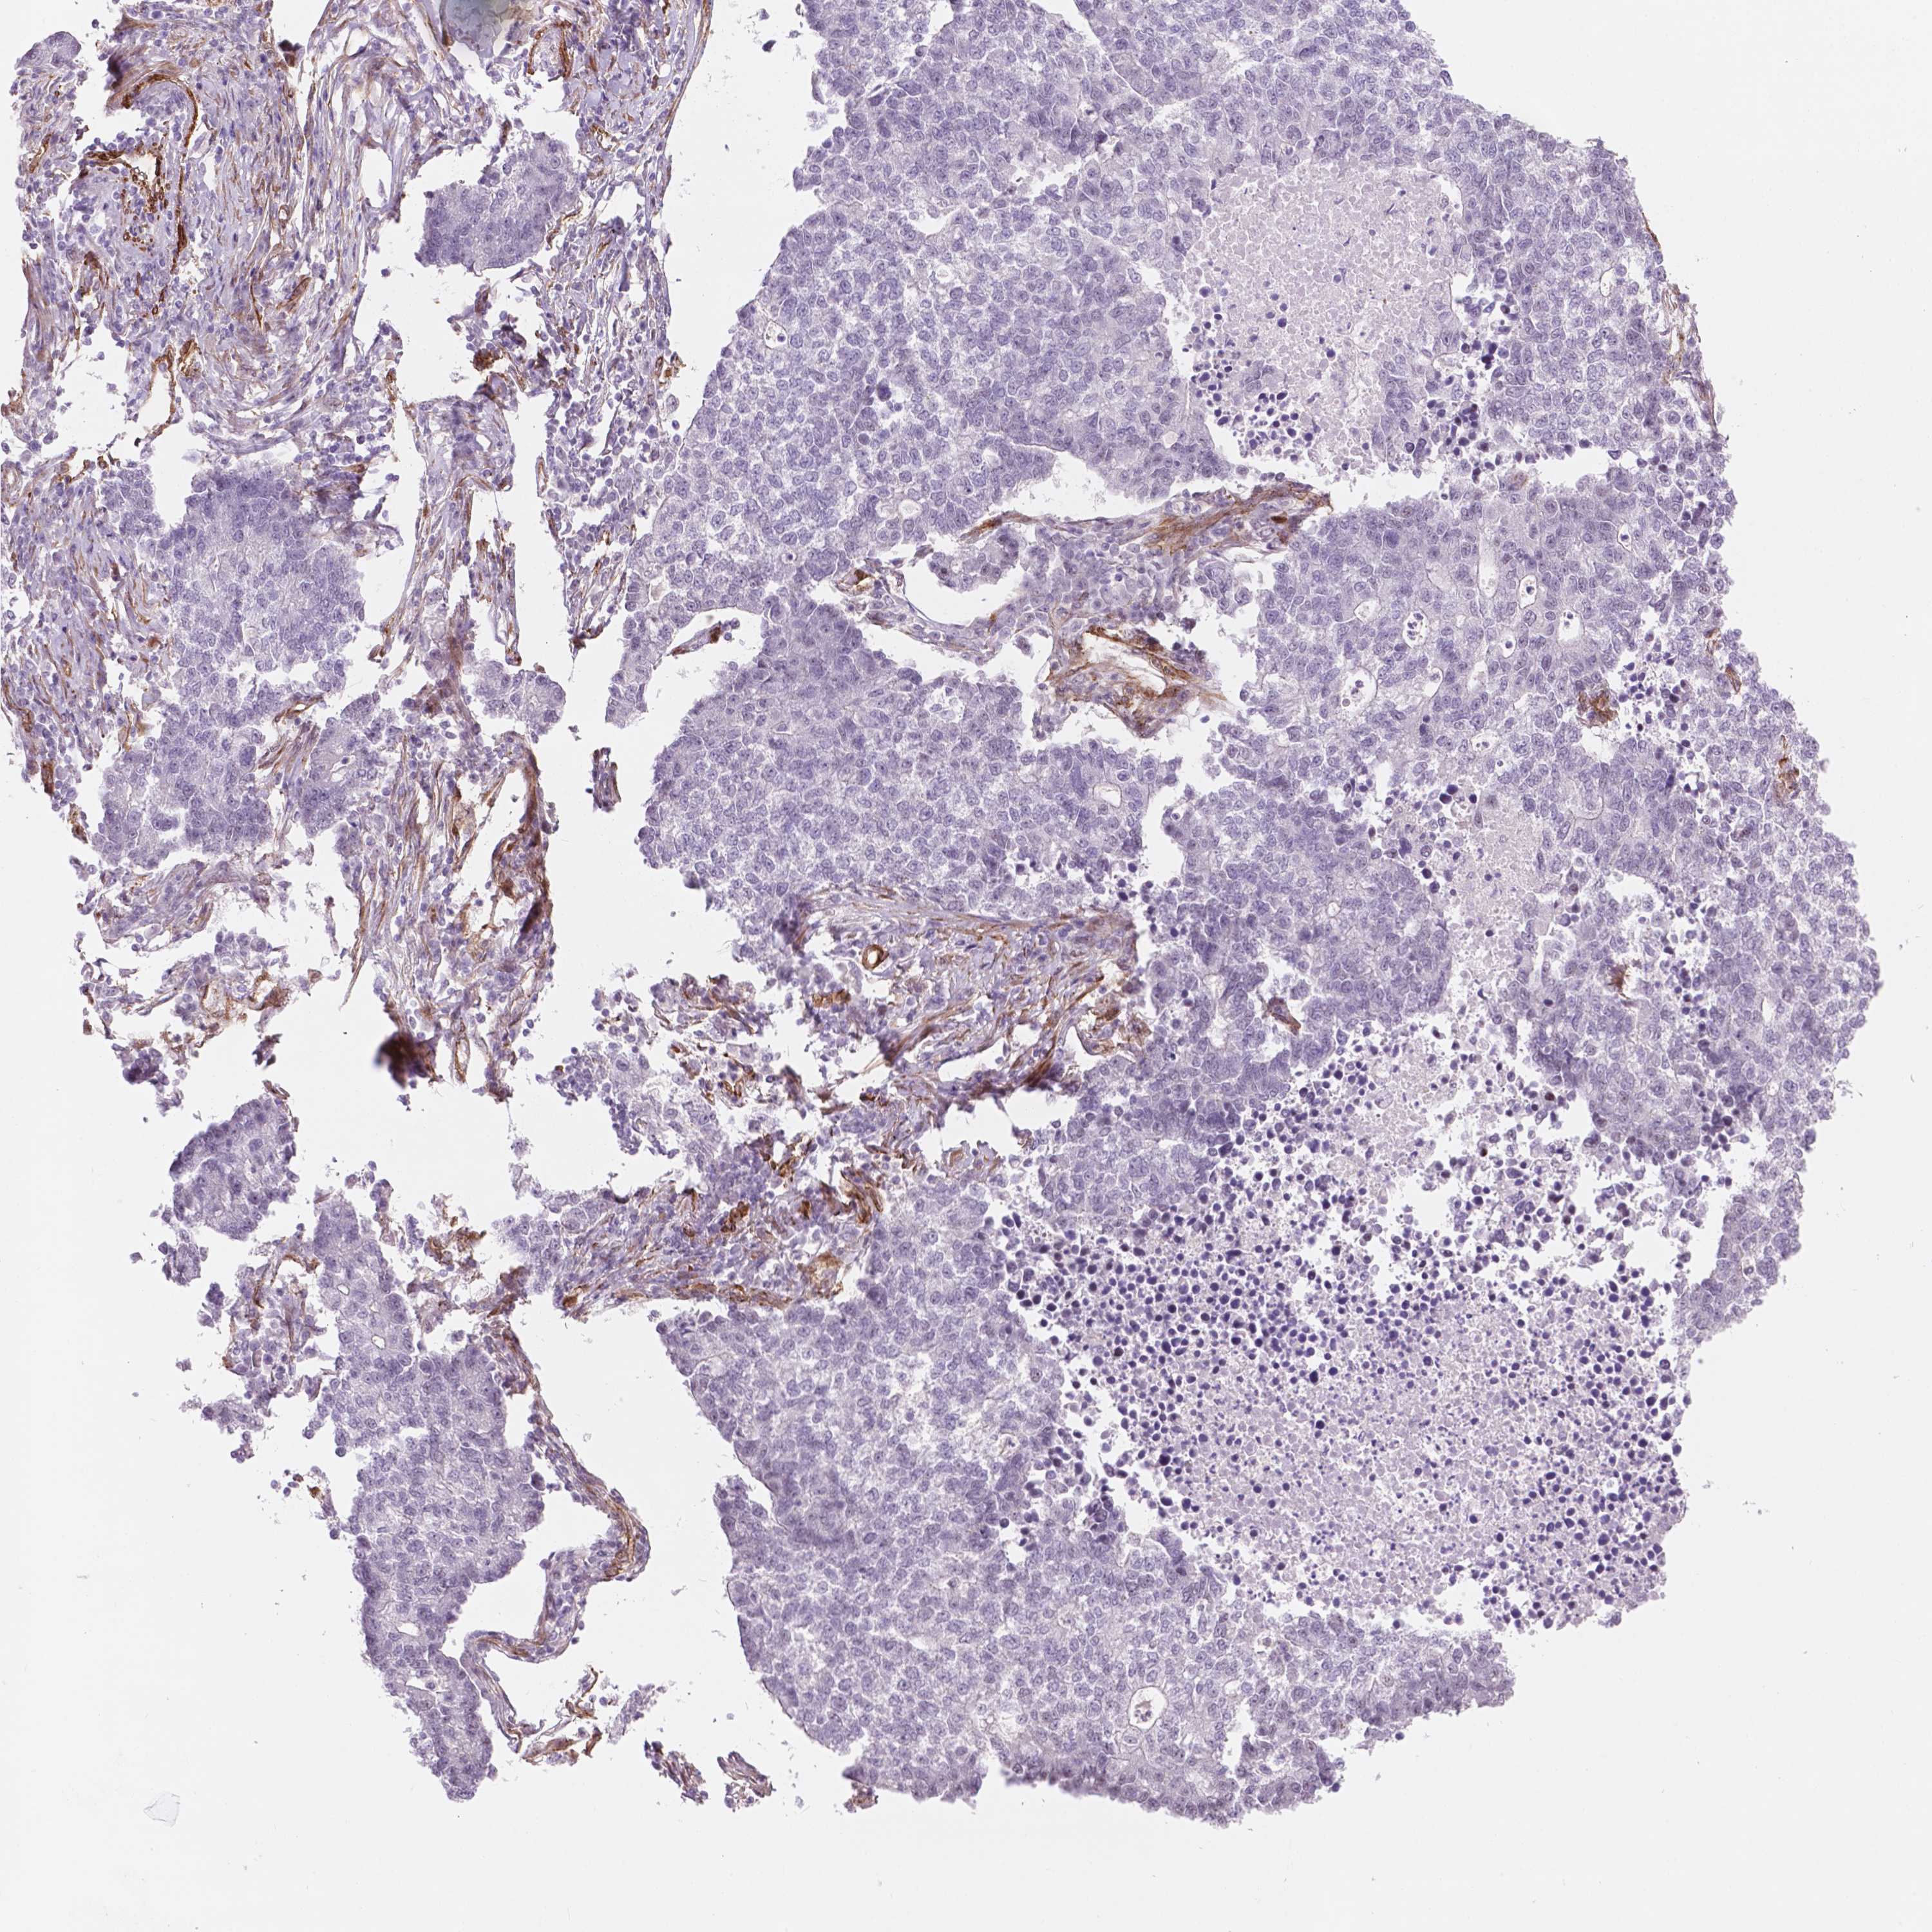

LUNG ADENOCARCINOMA (VALIDATION) - Interactive survival scatter ploti

The Survival Scatter plot shows the clinical status (i.e. dead or alive) for all individuals in the patient cohort, based on the same data that underlies the corresponding Kaplan-Meier plots. Patients that are alive at last time for follow-up are shown in blue and patients who have died during the study are shown in red.

The x-axis shows the expression levels (FPKM) of the investigated gene in the tumor tissue at the time of diagnosis. The y-axis shows the follow-up time after diagnosis (years). Both axes are complimented with kernel density curves demonstrating the data density over the axes. The top density plot shows the expression levels (FPKM) distribution among dead (red) and alive patients (blue). The right density plot shows the data density of the survived years of dead patients with high and low expression levels respectively, stratified using the cutoff indicated by the vertical dashed line through the Survival Scatter plot. This cutoff is automatically defined based on the FPKM cutoff that minimizes the p-score. The cutoff can be changed by dragging the vertical line or by entering a cutoff value in the square labeled "Current cut-off".

Under the Survival Scatter plot the p-score landscape (black curve; left axis) is shown together with dead median separation (red curve; right axis). Dead median separation is the difference in median mRNA expression between patients who have died with high and low expression, respectively. It is calculated as follows: median FPKM expression of dead patients with high expression - median FPKM expression of dead patients with low expression. This is intended to aid the user in visually exploring custom cutoffs and the associated p-scores and dead median separation.

Individual patient data is displayed and can be filtered by clicking on one or more of the category buttons on the top of the page. Categories describing expression level and patient information include: high, low, alive, dead, female, male and tumor stages. The scale of the x-axis can be toggled between linear and log-scale by clicking on the "x log" button. Mouse-over function shows TCGA ID, patient information and mRNA expression (FPKM) for each patient.

& Survival analysisi

Kaplan-Meier plots summarize results from analysis of correlation between mRNA expression level and patient survival. Patients were divided based on level of expression into one of the two groups "low" (under cut off) or "high" (over cut off). X-axis shows time for survival (years) and y-axis shows the probability of survival, where 1.0 corresponds to 100 percent.

EGFL8 is not prognostic in Lung Adenocarcinoma (validation)

TCGA RNA samplesi

RNA-seq data is reported as average FPKM (number Fragments Per Kilobase of exon per Million reads), generated by the The Cancer Genome Atlas (TCGA) .

Normal distribution across the dataset is visualized with box plots, shown as median and 25th and 75th percentiles. Points are displayed as outliers if they are above or below 1.5 times the interquartile range. FPKM values of the individual samples are presented next to the box plot.

Average pTPM 0.1

Number of samples 105